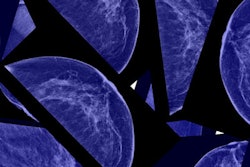

New European guidelines recommend that women be screened for breast cancer from ages 45 to 74 every two to three years because annual screening may be more harmful than beneficial. The guidelines pose a stark contrast to U.S. recommendations, which for the most part recommend annual screening.

For all age groups, annual screening reduced breast cancer mortality and showed lower interval cancer rates. However, annual screening also boosted overdiagnosis, false positives, and follow-ups with biopsies. What's more, annual screening carries a higher probability of radiation-induced breast cancer rates (6 in 100,000 versus 4 in 100,000 for biennial). For these reasons, the panel recommends biennial or triennial screening over annual screening.

Recommendations 10-11: Women ages 50 to 59 should be screened using digital mammography versus digital breast tomosynthesis (DBT) -- including DBT with synthesized 2D images.